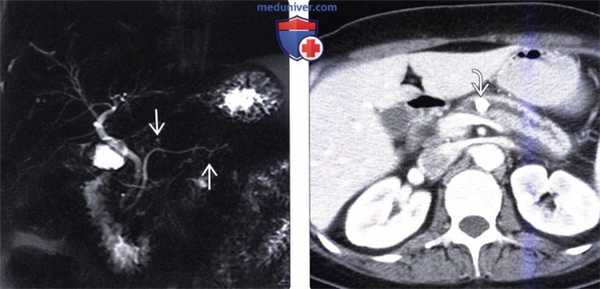

(Слева) На корональной МРХПГ (МIP-реконструкция) у пациента с хронической болью в животе определяется едва заметное расширение немногочисленных боковых ветвей панкреатического протока, что может являться ранним признаком хронического панкреатита; заключение о хроническом панкреатите у этого пациента впоследствии подтвердилось при эндоскопической ультрасонографии.

(Справа) На аксиальной КТ с контрастным усилением у пациента с известным хроническим панкреатитом алкогольной этиологии в расширенном главном панкреатическом протоке визуализируется отдельно лежащий камень большого размера Проток выглядит слегка деформированным и имеет вид «бус».